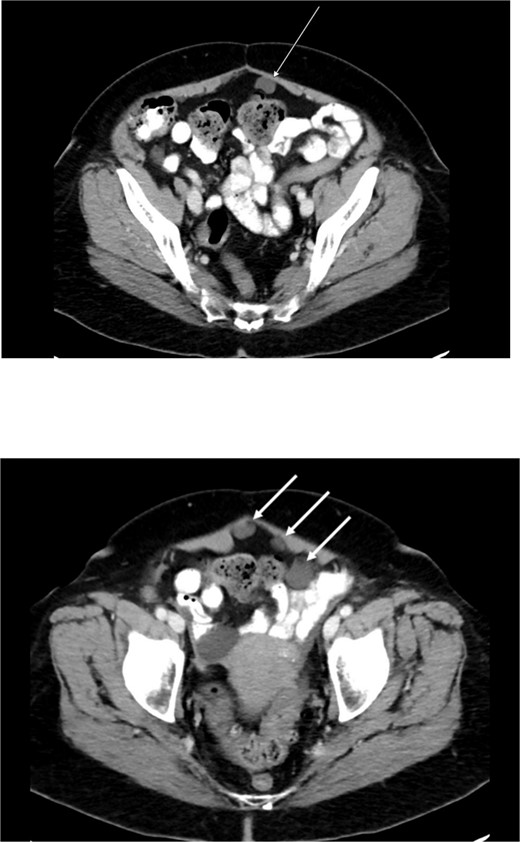

Diagnostic laparoscopy demonstrated multiple cystic lesions throughout the abdomen and pelvis (Figs 3 and 4). The gross appearance of these cysts was consistent with mucinous carcinomatosis. Laparoscopic excisional biopsy of several lesions was performed. Frozen section analysis revealed mucin but did not reveal evidence of metastatic adenocarcinoma. Colectomy was deferred due to concern for carcinomatosis, as if confirmed, she would likely be treated with neoadjuvant chemotherapy, restaging, followed by cytoreductive surgery (to include synchronous right colectomy) with heated intraperitoneal chemotherapy.

Intraoperative view of the pelvis: multiple cysts involving the peritoneum.